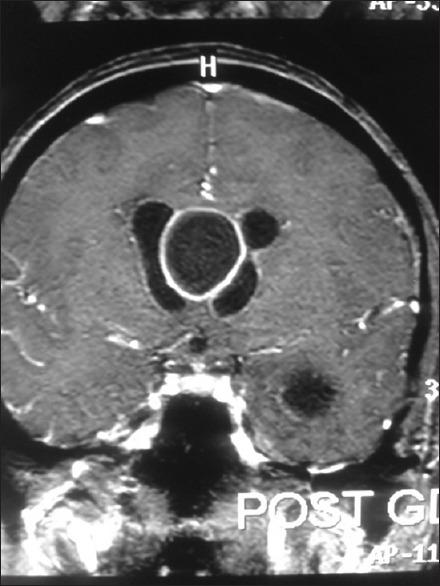

The cavum septum pellucidum (CSP) is defined as a crevice-like space of variable width between the left and right transparent septum. In this report, a rare case of pseudo primary abscess formed in the CSP due to ventriculitis is presented.

透明隔腔(CSP)被定义为左右透明隔之间宽度可变的缝隙样间隙。在本报告中,介绍了一例因脑室炎在透明隔腔形成假性原发性脓肿的罕见病例。